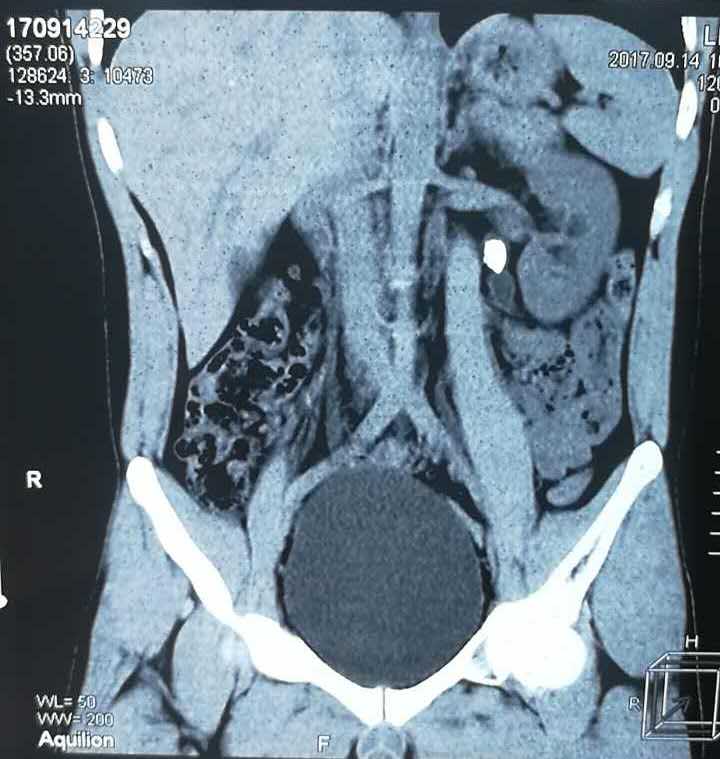

患者刘鹏 一例左输尿上段结石伴左多发小结石患者,体外碎石效果不佳,给予经皮肾镜碎石取石,手术总耗时约30分钟,术后未予留置肾造瘘管(无管化),一次清除结石。

术后三天患者即出院,大大缩短住院时间,患者痛苦更少。